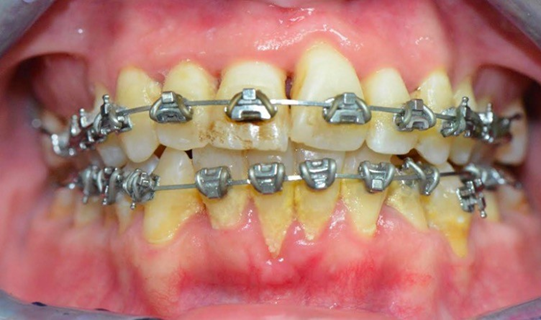

Four adult patients, seen by four different clinicians presented for orthodontic treatment with new orthodontic diagnostic terms of maxillary and mandibular hypoplasia with localized Orthodontosis and Orthodontitis (Figures 4–7),30 were successfully treated with the patented systems of FASTBRACES® Technologies. It is important to note that the universal orthodontic goal and accompanying treatment should be to successfully treat the biologically based diagnosis of the alveolar bone clinical morphology within a patient’s natural stable occlusion and morphologic appearance. Figure 4 holds particular significance as it sheds light on the complex nature of periodontal conditions, which involve multiple critical parameters. Notably, it reinforces the existing literature by demonstrating that the microbial flora surrounding tooth #25 or in an area already compromised by alveolar hypoplasia can progressively and rapidly deteriorate the alveolar bone.

Figure 5 A&B Pretreatment of mild cupping / alveolar bone deficiency of the maxillary right premolars (arrow) and severe cupping of the maxillary maxillary right lateral incisor (arrow).

Figure 5 C&D Post treatment of mild cupping / alveolar bone deficiency of the maxillary right premolars and severe cupping of the maxillary right lateral incisor.

However, it is important to provide additional context regarding the initial treatment approach, which involved a gingival graft to address the periodontal dehiscence. However, by forgoing traditional periodontal treatment and opting for an orthodontic alveolar bone restoration protocol with FASTBRACES® Technologies, partial coverage of the exposed tooth by alveolar bone was achieved. This suggests the convergence and potential overlap between periodontics and orthodontic alveolar bone restoration, highlighting the need for interdisciplinary collaboration. A FASTBRACES® Technologies intervention restores alveolar bone architecture, naturally aligns the teeth thereby also altering the highly pathogenic microbial flora. This is because the universal constant is the alveolar bone clinical morphology with treatment directed towards the alveolar bone deficiencies when present. These four cases are successful examples of non- extraction orthodontic treatment with the patented systems of FASTBRACES® Technologies which appropriately address the relevant deficiencies in the alveolar bone clinical morphology while maintaining a 1 to 3mm overbite /overjet and not changing the patient’s natural molar relation. The authors believe the systems of FASTBRACES® Technologies induce alveolar bone remodeling by moving the tooth roots towards their natural properly erupted positions from the onset of treatment.